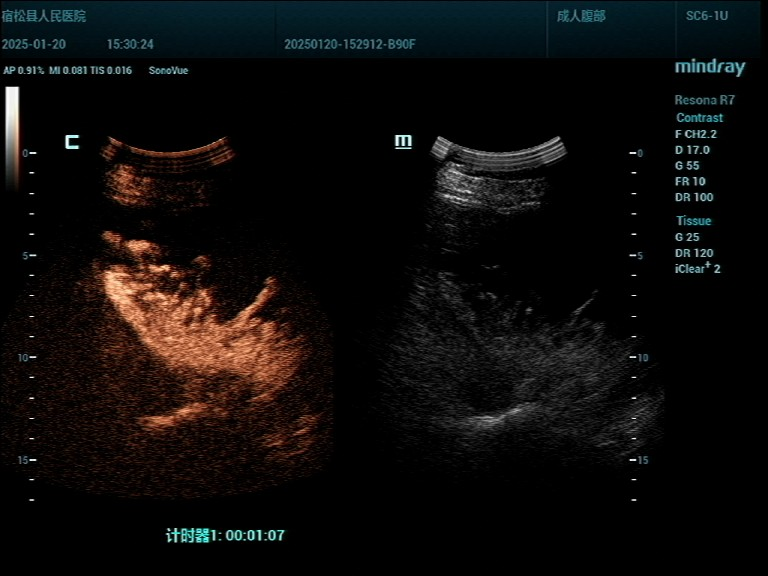

手术中,经超声精确定位,局部麻醉,有丰富介入与穿刺经验的吴飞医生和杨翠桥护士熟练操作配合,穿刺引流管精准到位,抽出20ml囊液做蛋白定性试验(+),囊内注入造影剂、超声造影显示囊肿与肝内胆管不相通,由于囊肿过于巨大,一次抽完对身体不利,计划分多次引流,总共引流量达1000ml,再用硬化剂冲洗囊腔,使囊壁纤维化不再分泌囊液而达到治疗目的。

▲1.治疗前超声显示 ▲2.穿刺针经皮肝进入囊肿内

▲5.术中超声造影显示与肝内胆管不相通 ▲6.治疗结束后超声显示囊肿缩小至不足1cm